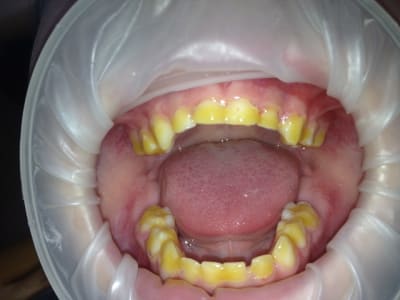

Jamais ces merdes de cotons salivaires. Essayes optragate +linguafix et tu ne travailles plus dans une caverne, que la lumière soit ! Et au boulot !)))))))

Tu as des patients terrifiants Chicot! On voit qu'ils ne viennent pas pour rien ;)

Oui j'ai quand meme été controlé sur un de ces patients (CMU tiens étrange ?) pour voir si je n'abusais pas ! lol ! Pas le premier hein ! c'est mon fils à 5 ans avec du duraphat (le seul et unique qui y a eu droit, tiens ? étrange) .))))))))